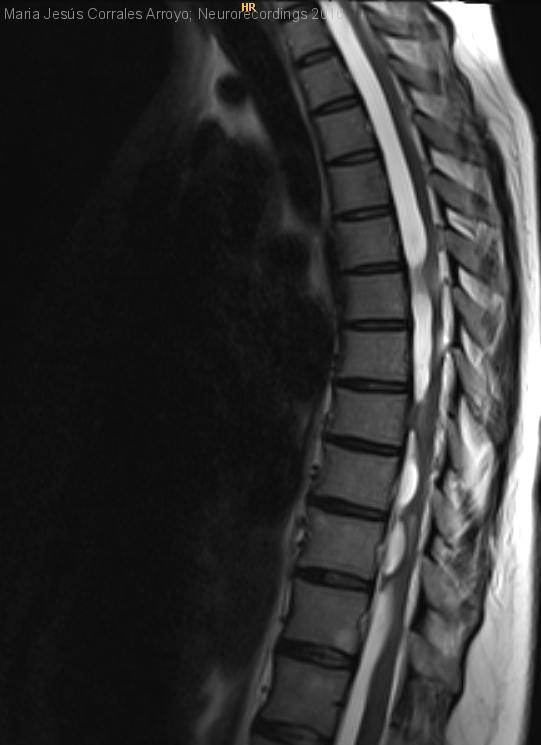

Mujer | 34 años

Diagnóstico final: Aracnoiditis adhesiva crónica yatrogénica.

Paciente de 34 años con cuadro progresivo de dos meses de evolución con torpeza y alteración en la marcha, acompañado de debilidad en MM.II. La semana previa a la consulta asocia alteración sensitiva con hipoestesia...